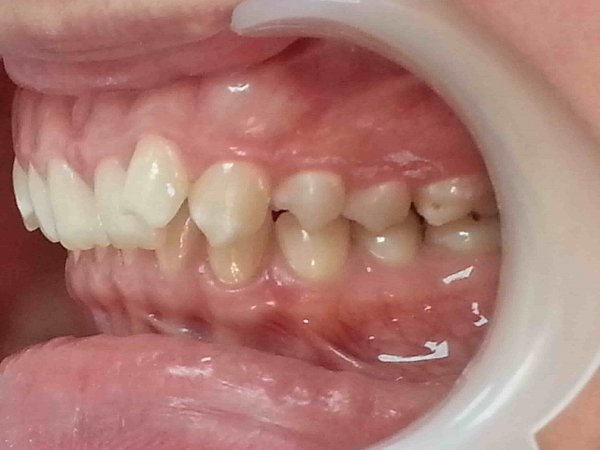

Пациентка 16 лет. Обратилась с жалобой на вертикальную щель между верхней и нижней челюстями.

Объективно: Вертикальная дизокклюзия 4 мм. Перекрестная окклюзия справа, смещение центральной линии нижней челюсти вправо. Щелчок в правом ВНЧС, неправильное положение языка.

План лечения:

1)удаление всех зубов мудрости;

2)устранение вертикальной щели и перекрестной оккклюзии с помощью техники многопетлевой дуги

3)ношение эластических тяг

4)Работа с логопедом для нормализации положения языка.

Достигнуты результаты за 10 месяцев:

1)устраниение вертикальной щели и перекрестной окклюзии справа;

2)выровнена центральная линия нижней челюсти;

3)устранение щелчка в правом ВНЧС;

4)пациентка работает с логопедом для нормализации положения языка.